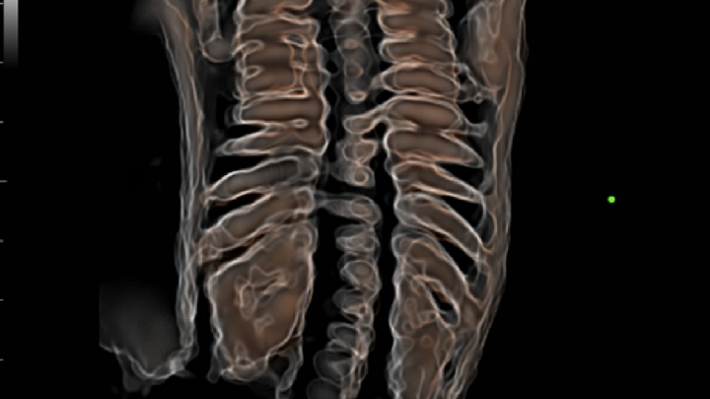

УЗИ-аппарат Mindray DC-70 — это современная ультразвуковая система экспертного класса, предназначенная для проведения диагностических исследований в различных областях медицины, включая кардиологию, акушерство и гинекологию, абдоминальные и сосудистые исследования. Аппарат сочетает высокое качество изображения с широким набором функциональных возможностей, что делает его эффективным инструментом для диагностики.

• Многофункциональность: Поддержка различных режимов сканирования, включая 2D, 3D/4D, цветное допплеровское картирование и другие, позволяет использовать аппарат для широкого спектра медицинских задач;

• iLive™ — технология 3D/4D-визуализации с функцией постобработки изображений;

• iPage™ — мультисрезовое томографическое отображение с регулировкой толщины среза;

Изображения